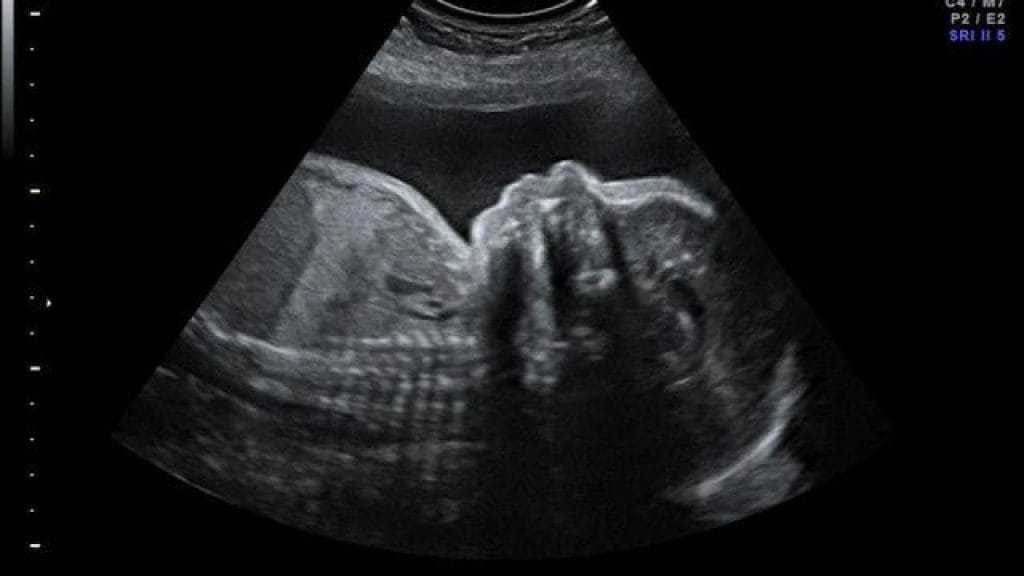

22. Haftada Ultrason Görüntüsünde Bebek Nasıl Görünür?

Gebeliğin 22. haftasında yapılan ultrason, hem bebeğin gelişimini hem de organlarının işlevselliğini değerlendirmek açısından oldukça önemlidir. Bu dönem genellikle ayrıntılı ultrason (detaylı anatomi taraması) haftası olarak bilinir. Çünkü bebek artık yeterince büyümüş ve iç organları gözlemlenebilir hale gelmiştir.

Ultrason cihazında bebek, artık minyatür bir insan şeklindedir. Kafa, yüz hatları, kollar, bacaklar ve hatta parmak detayları net biçimde seçilebilir. Kalp dört odacıklı yapısıyla atarken, mide, böbrekler, mesane ve omurga gibi organlar da görülebilir. Ayrıca bu haftada bebeğin cinsiyeti büyük oranda kesinleşmiştir.

Bu haftada ultrason sırasında bebeğin hareketli olduğunu görmek yaygındır. Hatta bebek çoğu zaman dönme, tekme atma veya parmak emme gibi hareketler yapar. Ultrason görüntülerinde bu hareketler, hem anne hem de baba adayına büyük bir heyecan yaşatır.

Ayrıca detaylı ultrason, sadece bebeğin gelişimini görmekle kalmaz; plasenta konumu, göbek kordonu yapısı ve amniyon sıvısı miktarı da bu inceleme sırasında değerlendirilir. Bu bilgiler, gebeliğin sağlıklı ilerleyip ilerlemediğini anlamak açısından kritik öneme sahiptir.

Ultrason sonuçları normal olduğunda, anne adayı bir sonraki kontrolüne kadar rahat bir dönem geçirir. Ancak herhangi bir şüpheli durum varsa, doktor ek incelemeler veya takip ultrasonları önerebilir.